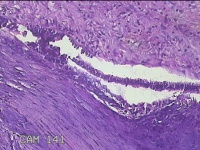

右侧卵巢囊肿

性别

女

年龄

36岁

临床诊断

一般病史

发现双侧附件囊肿1年。

标本名称

大体所见

灰白暗红色囊壁样组织2.5x2x0.3cm一块,表面光滑,部分已切开,囊内容物已流失,囊壁厚0.2cm。

考虑:子宫内膜异位囊肿。